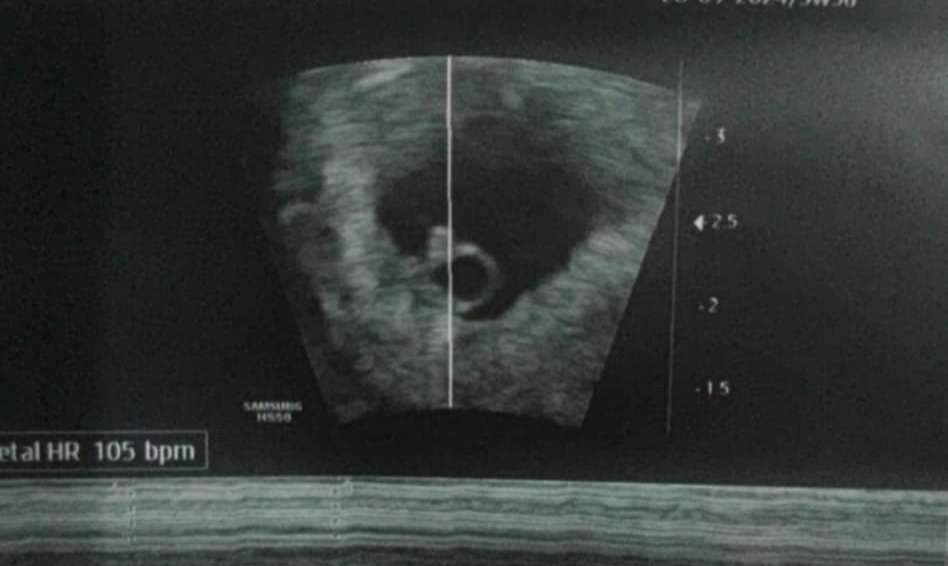

I takie jeszcze, zarodek 3.87 mm

• 050b2cd5-cf51-4546-8611-22c3b2cd83a7.jpeg

050b2cd5-cf51-4546-8611-22c3b2cd83a7.jpeg

27,9 KB · Wyświetleń: 65